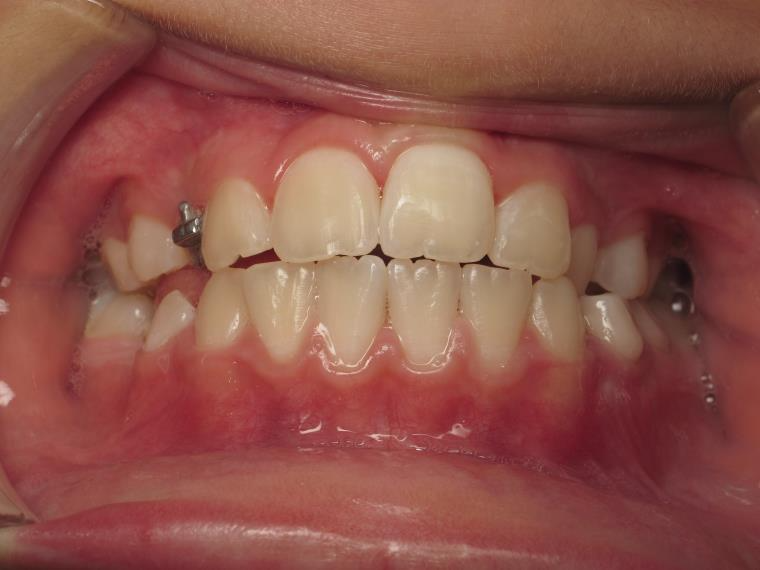

sectionnel multibagues pendant 25 mois

bilan début et fin de traitement